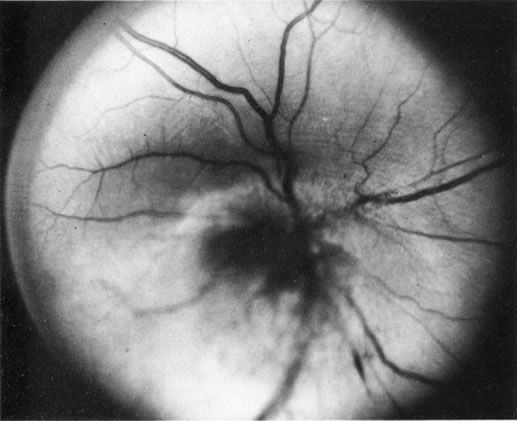

Some retinal dystrophies and degenerative processes can simulate a retinochoroiditis. Vitreous cells may occur in cases of retinitis pigmentosa. Pigmented paravenous retinochoroidal atrophy has a distinctive pattern of pigmentary deposits surrounding retinal veins; it may occur as an idiopathic degenerative disorder or sometimes as a sequela of ocular sarcoid. Fundus flavimaculatus is a rare autosomal recessive dystrophy that is usually detected in the third decade of life. It produces typical comma-shaped, yellowish retinal pigment epithelial opacities in the posterior pole, but it does not involve the macula. It can simulate a diffuse choroiditis (Fig. 24). Myopic degeneration can produce small, white, posterior pole spots that can simulate a posterior choroiditis. Peripheral fundus “paving stone” degeneration is rarely confused with an inflammatory process. These lesions show no evidence of retinal or vitreal inflammation and are quite common.54

Fig. 24. Fundus flavimaculatus. Note comma- or fish-shaped yellowish Figures at the level of pigment epithelium.